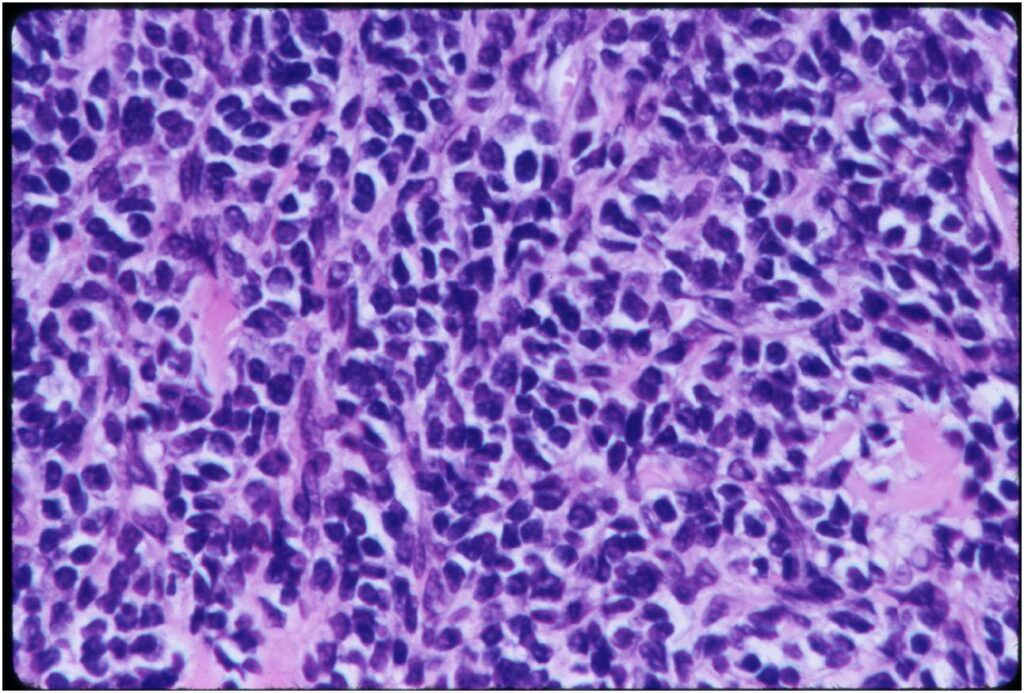

Microscopic Pathology

- Neoplastic cells may be small, round, oval, or spindle shaped

- Undifferentiated mesenchymal cells similar to Ewing sarcoma

- May contain islands of collagen resembling osteoid

- Lesions are vascular and often have large, anastomosing vessels that impart hemangiopericytoma-like pattern